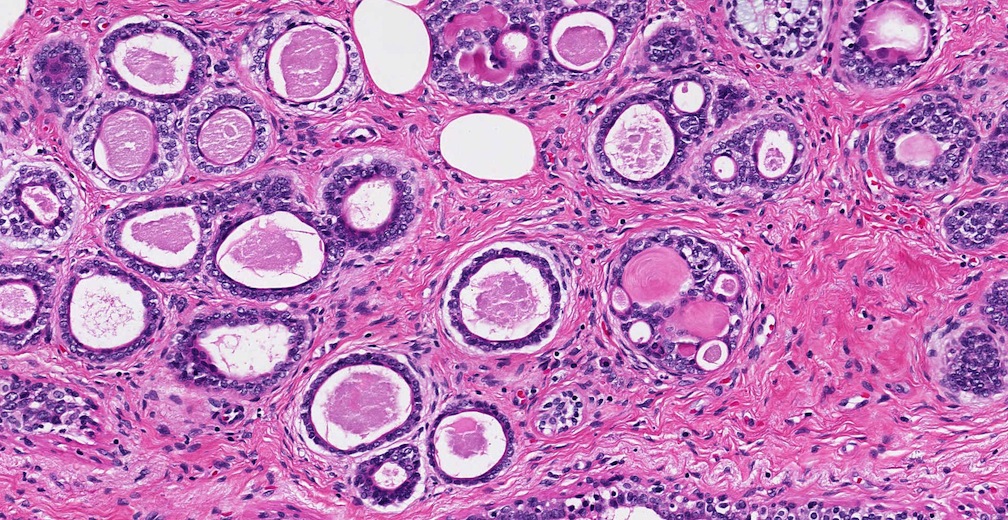

In order to choose the type of diagnostic test, various factors may be considered which include the age of the individual, their medical condition, earlier medical tests, the type of symptoms evident and the form of cancer suspected. A biopsy is the only method of confirming the presence of cancer. This involves the removal of a small section of the affected tissue using either a fine needle biopsy or the removal of a part of the tumour which is examined under the microscope for abnormalities. Some of the other diagnostic tests can include CT scan, MRI scan to measure the size of the mass and a PET scan to observe the images of various organs along with the tissues of the body.